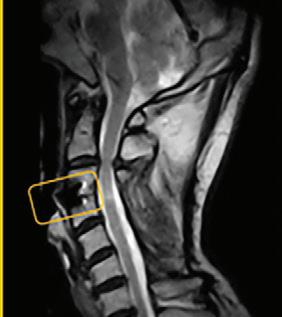

The evolution of MRI

What a weight-bearing MRI reveals vs. a Supine MRI

G-scan Brio Reveals What Supine MRI Misses

Conventional MRI may not demonstrate the pathology related to these symptoms, but G-scan Brio gives you a new point of view so you can accurately diagnose MSK pathologies affected by weight-bearing position.

More Detail, Better Accuracy, Greater Confidence

G-scan Brio: Adds Weight To Your Diagnosis

The G-scan Bro is superior to other MRIs because both the magnet and patient can rotate from 0 to 90 degrees.

G-scan Brio offers a revolutionary MRI approach that increases diagnostic accuracy and confidence for musculoskeletal applications.